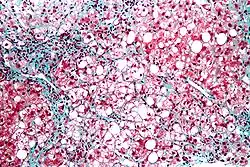

| Micrograph showing a fatty liver (macrovesicular steatosis), as seen in metabolic dysfunction–associated steatotic liver disease. Trichrome stain. | |

The fatty change represents the intracytoplasmatic accumulation of triglycerides (neutral fats). At the beginning, the hepatocytes present small fat vacuoles (liposomes) around the nucleus (microvesicular fatty change). In this stage, liver cells are filled with multiple fat droplets that do not displace the centrally located nucleus. In the late stages, the size of the vacuoles increases, pushing the nucleus to the periphery of the cell, giving a characteristic signet ring appearance (macrovesicular fatty change). These vesicles are well-delineated and optically "empty" because fats dissolve during tissue processing. Large vacuoles may coalesce and produce fatty cysts, which are irreversible lesions. Macrovesicular steatosis is the most common form and is typically associated with alcohol, diabetes, obesity, and corticosteroids. Acute fatty liver of pregnancy and Reye's syndrome are examples of severe liver disease caused by microvesicular fatty change.[19] The diagnosis of steatosis is made when fat in the liver exceeds 5–10% by weight.[13][20][21]